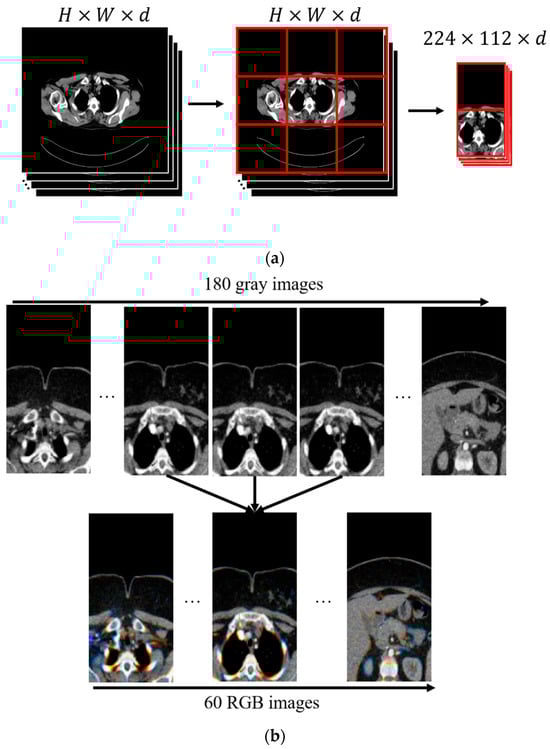

In the proposed preprocessing step, the first stage involves cropping the image based on the possible anatomical location where the tumor (thymoma) is commonly observed. The thymoma tumor typically occurs in the mediastinal region, that is, between the lungs within the thoracic cavity. Based on this, as shown in Figure 2a, the CT image is divided into a 3 × 3 grid. As a result of this division, the images in the first and second rows of the second column are cropped and selected for analysis. This approach directly focuses the model’s attention on areas where tumor formation is most likely, thereby increasing data efficiency. In this way, the limited data is utilized in the most efficient manner, and the diagnostic sensitivity of the model is also significantly improved. The second step in preprocessing involves reducing the number of CT slices (Figure 2b). Here, direct resizing was avoided because it could result in the loss of the limited number of tumor-containing slices. Additionally, since there is generally a high degree of similarity between slices, anomalies such as tumors can often be detected from the differences between them. Therefore, to reduce the data without losing details between slices, three consecutive grayscale slices were combined to create a three-channel (RGB-like) image. In this way, the number of slices is reduced without data loss, while also obtaining an input size suitable for the pre-trained VGG network architecture.

Figure 2. Pre-processing stage of thymoma images. (a) Mediastinal region cropping using a 3 × 3 grid; (b) CT slice stacking.